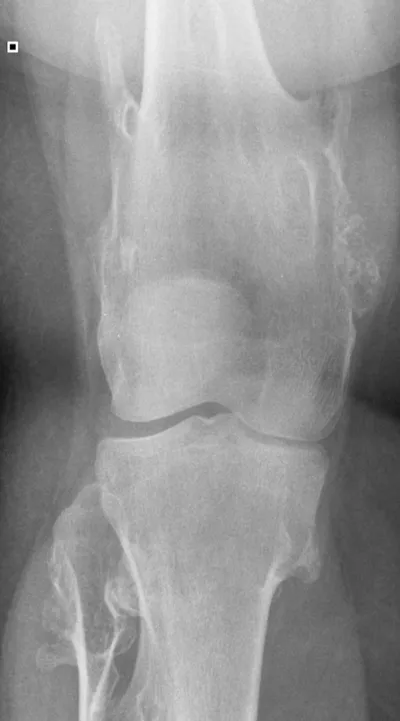

Dysplasia Radiology Images

Browse 5 medical images tagged with dysplasia. This collection includes various imaging modalities for medical education and reference.

- This collection contains 5 radiology images related to dysplasia, including various imaging modalities such as X-rays, MRIs, CT scans, and ultrasound images commonly used in medical diagnosis and education.